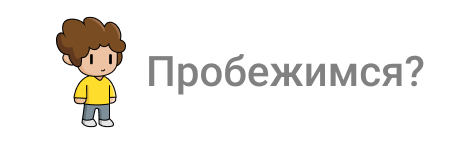

Балку получил из фрезерного центра, теперь надо её проверить на качество "посадки" на аналоги имплантов и в случае если будет баланс припассовать.

Титановый каркас "сидит" как надо не качается и не балансирует; не только на лабораторной модели, но и в полости рта — можно продолжать.